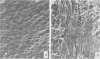

Autogenous canine jugular veins were stored in 15% dimethyl sulfoxide (DMSO) in liquid nitrogen vapor for one to 28 days and then implanted in the carotid artery as autografts. The patency rate at one year was 62.5-87.5%. The patency rate of fresh jugular vein autografts placed in the carotid artery for one year was 75%. Similar autografts stored in liquid nitrogen vapor for one to 28 days without the cryopreservative DMSO exhibited a zero to 12.5% patency rate at one year. Scanning electron microscope studies revealed preservation of theendothelium in DMSO protected veins and a damaged or sloughed endothelium in veins frozen without DMSO cryopreservation.